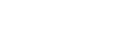

Follow-up chest CT showed similar peribronchiolar nodules; the noted consolidations persisted at both the upper and middle lobes of the lung (Figure 2). The 18FDG-PET CT scan showed mild increased uptake consistent with glucose metabolism the peak SUV was 1.5 at the RUL and 1.6 at the RML (Figure 3). In the 2 hour delayed views, the peak SUV was 1.6 at the RUL and 1.2 at the RML. Percutaneous CT-guided needle aspiration biopsy was performed targeting the consolidation area in the RML. However, the biopsy was insufficient for a diagnosis. Therefore, a VATS biopsy was planned of the consolidation area in the RML.

Figure┬Ā2

Follow-up chest CT 2 months after the initial visit reveals peribronchial consolidation (A), and marked bronchial wall thickening (B) in the right middle lobe lung field.